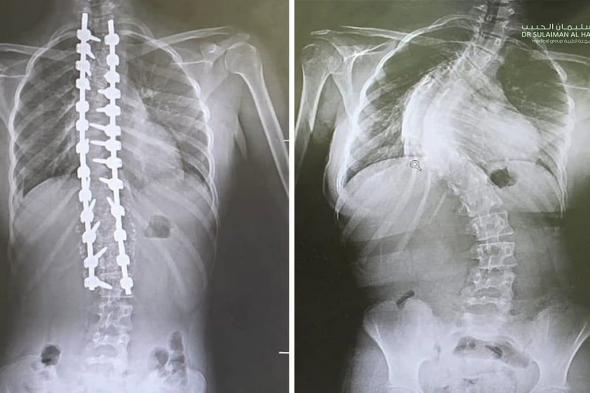

مستشفى الدكتور سليمان الحبيب بالقصيم يجرى عملية ناجحة لتقويم "جنف" بزاوية "95" درجة